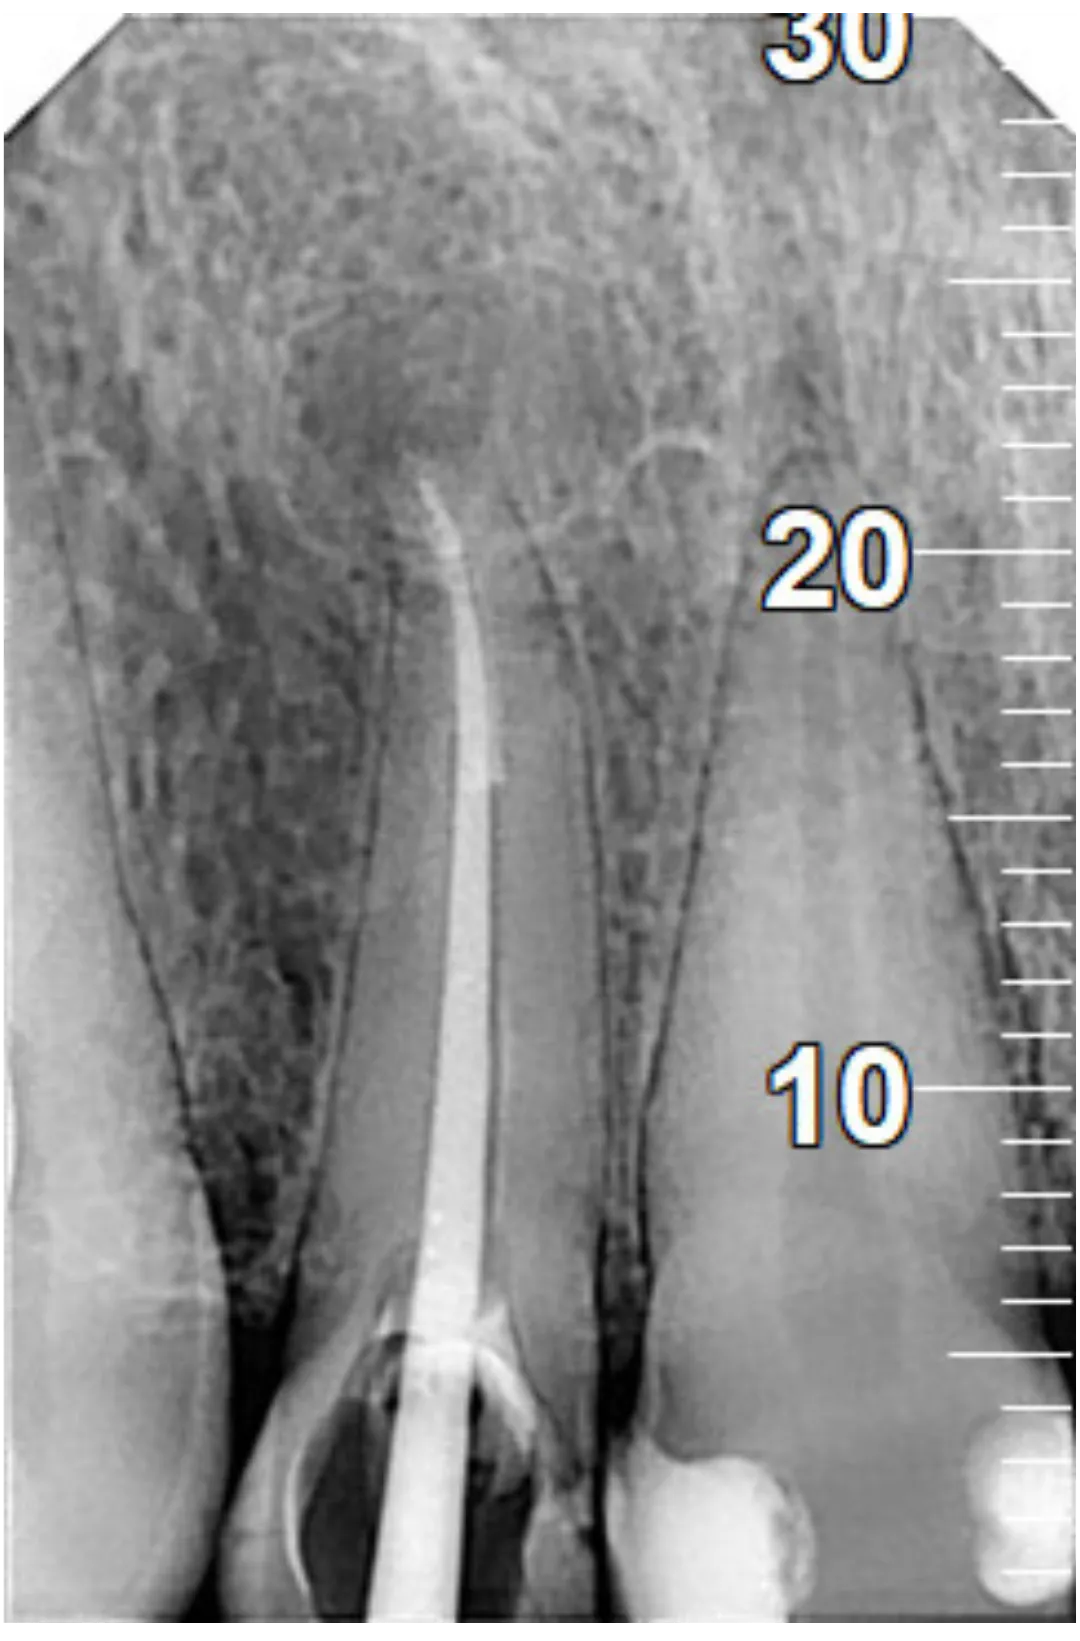

RXDC efikasnost proizlazi iz kombinacije napredne tehnologije i izvanredne sposobnosti za proizvodnju slika visoke definicije. RXDC X- ray uređaj pruža vrhunske performanse, praktičnost i tehnologiju. RXDC se odlikuje generatorom konstantnog potencijala visoke frekvencije (DC) i vrlo malom fokalnom tačkom (0,4 mm) koja omogućava oštre i detaljne slike, istovremeno osiguravajući radnu udobnost i niske doze zračenja za pacijenta.

Veće performanse sa RXDC, rendgenskim uređajem koji kombinuje slike visoke definicije, ergonomski dizajn i niske doze zračenja.

SUPERIORNA DIJAGNOSTIČKA KVALITETA Dobijena u samo nekoliko jednostavnih koraka, sve slike su visoke rezolucije.

NAPREDNA TEHNOLOGIJA

NewTom RXDC rendgenski uređaj visoke frekvencije baziran je na NewTom-ovom znanju, sa udaljenošću izvora od 30 cm i fokalnom tačkom od 0,4 mm.